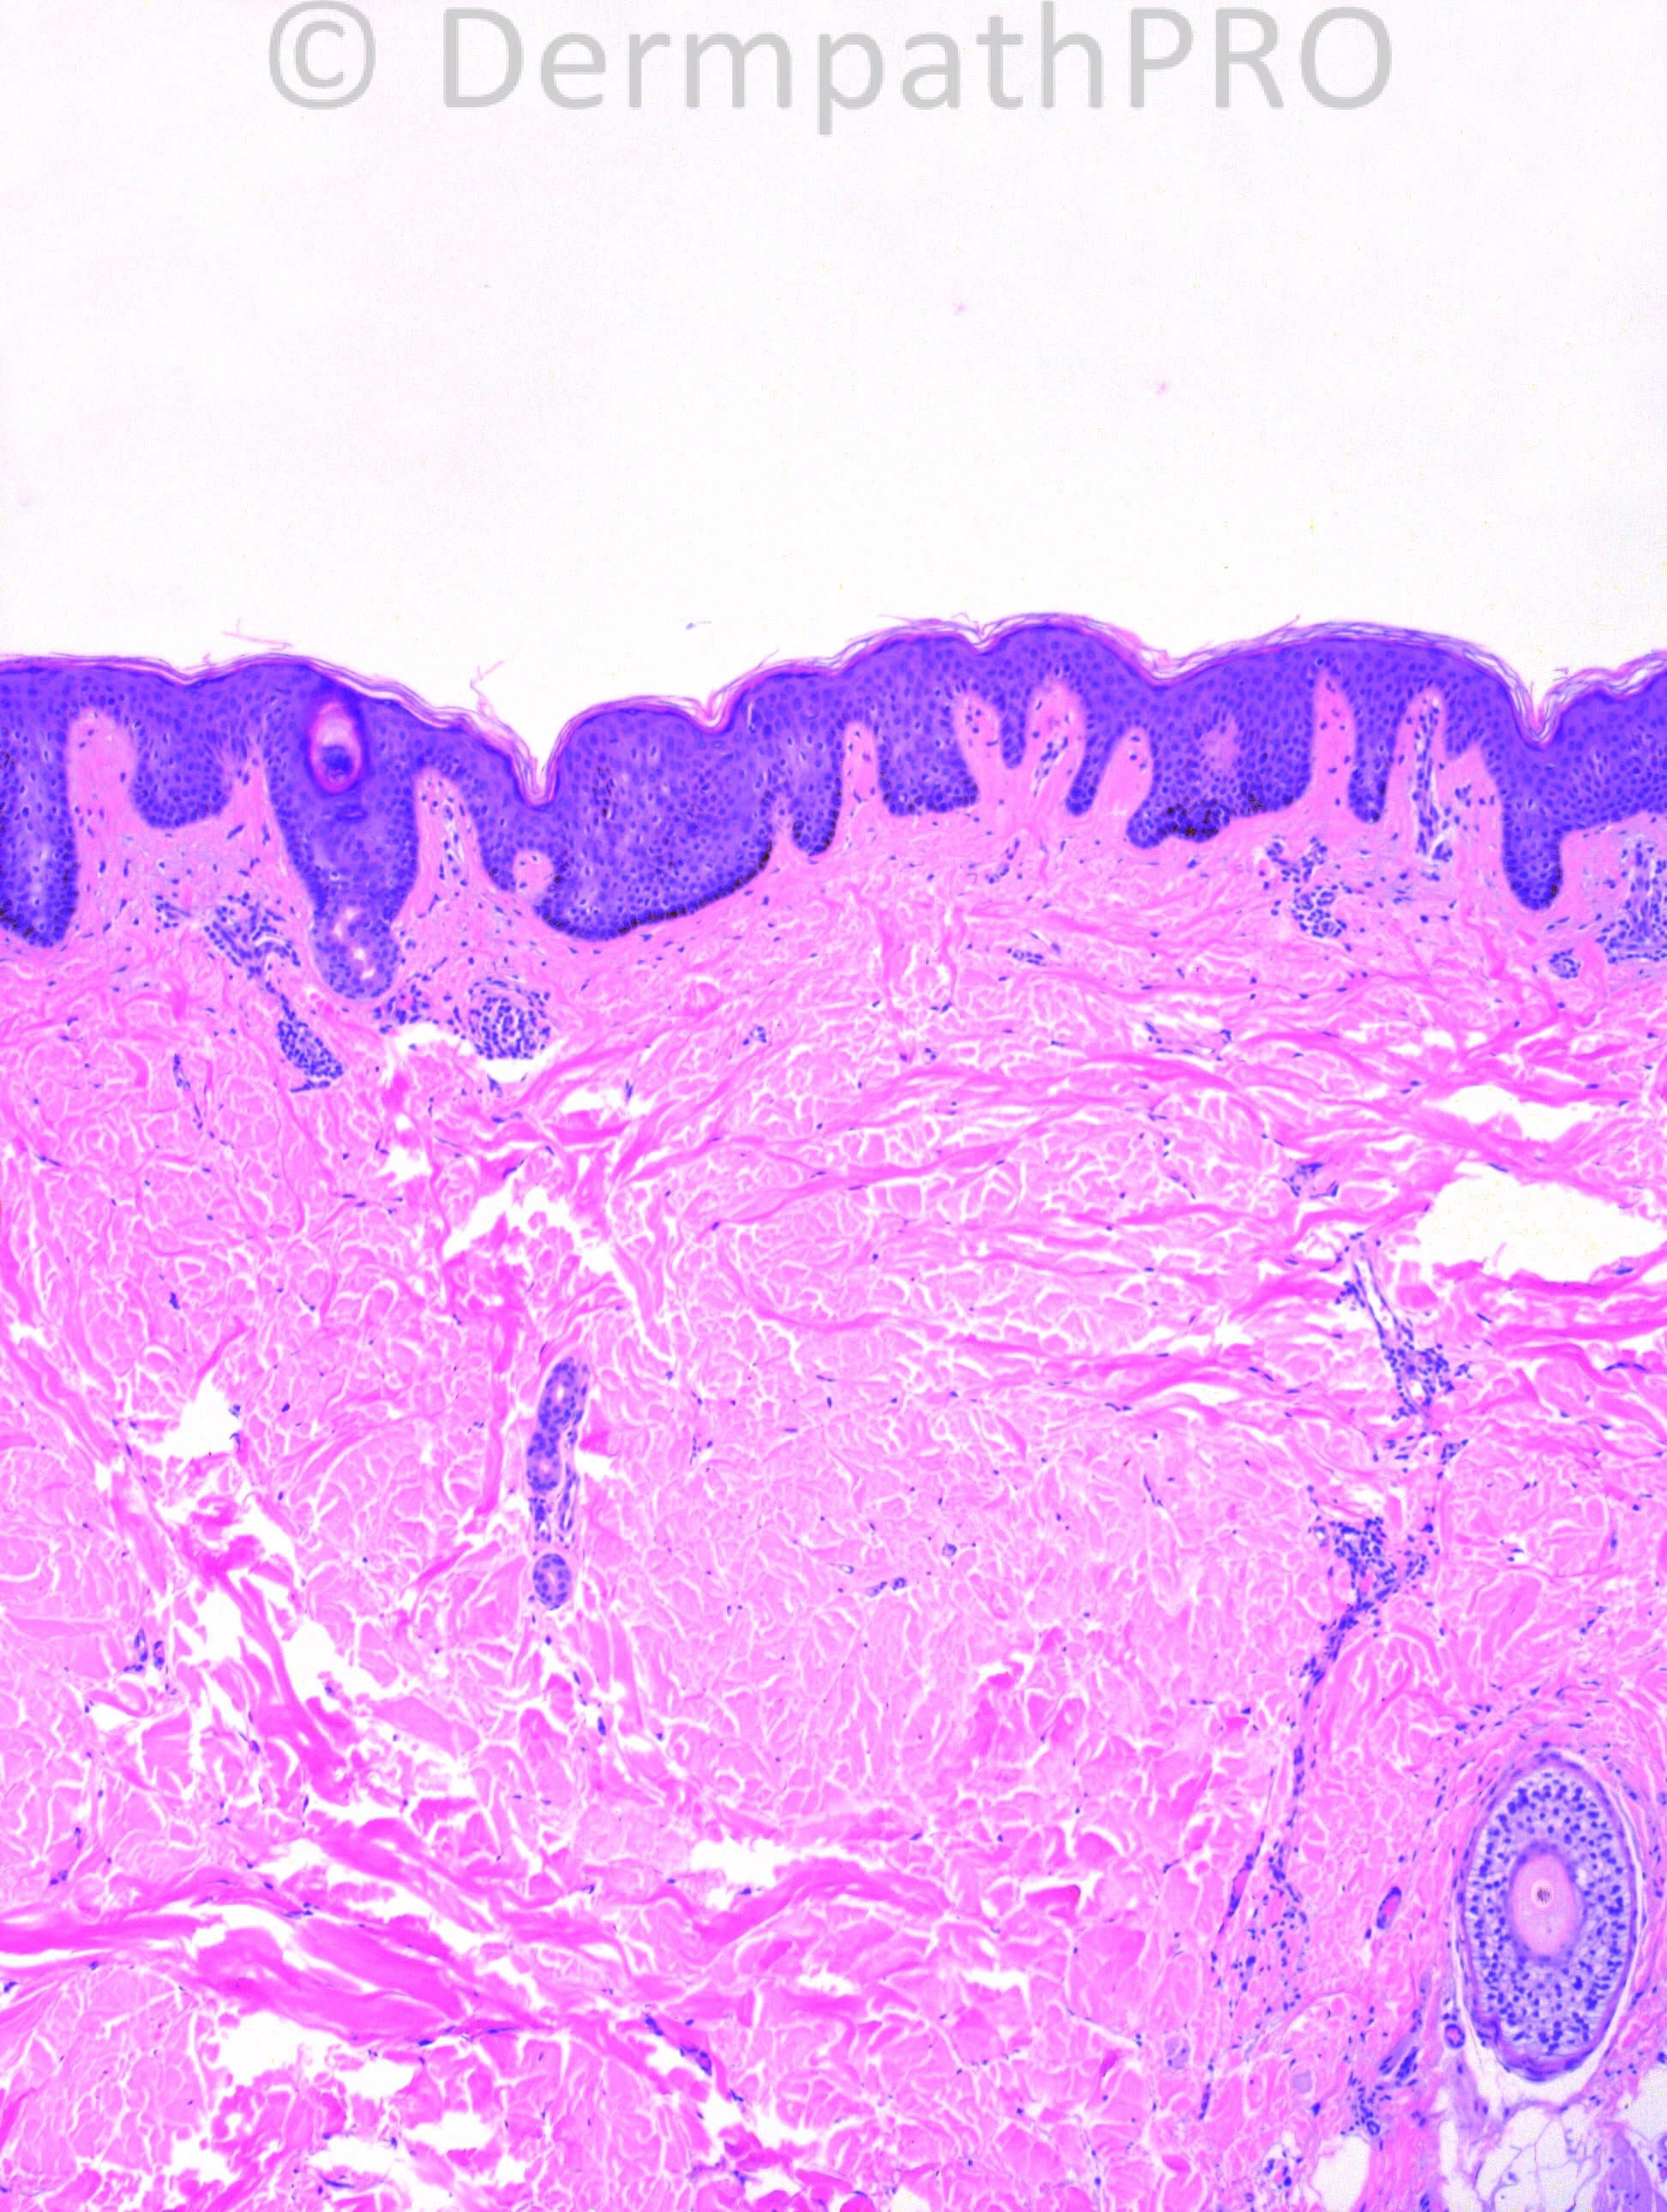

52 years-old female with left back lesion: a dimpled, soft plaque.

Case posted by Dr. Hafeez Diwan.